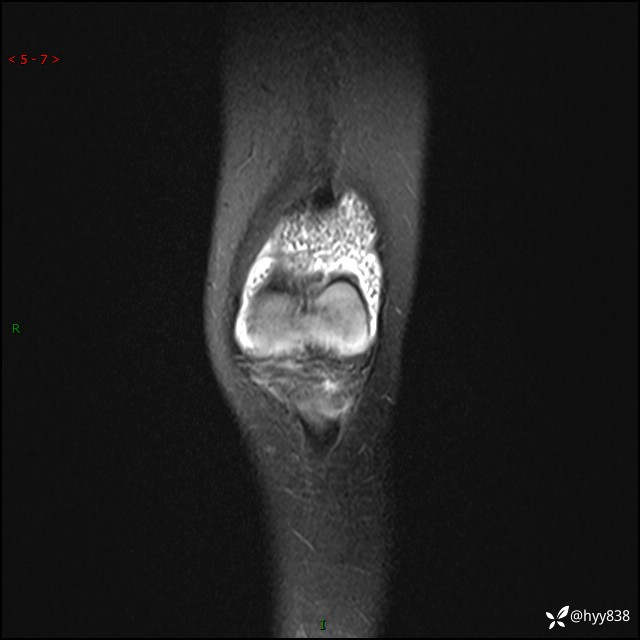

现病史:患儿1月前无明显诱因出现左下肢跛行,伴左膝关节红肿,无发热、咳嗽、恶心、呕吐等症,于当地医院就诊行X线片未提示异常,今至我院门诊就诊,门诊医师拟“跛行待查”收入院。 病后,患儿精神、食欲可,睡眠欠安,大小便通畅,体力体重无明显下降。

左膝MRI平扫